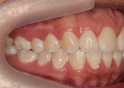

Classe II div 1, articulé croisé postérieur, surplomb accru, déviation de la ligne médiane maxillaire, rotations d'encombrement

Résultats obtenus

- Relation de classe I obtenue

- Guidage fonctionnel des canines des deux côtés

- Articulé postérieur corrigé

- Surplomb et recouvrement normaux obtenus

- Surplomb amélioré

- Lignes médianes coïncidentes

- Bonne inclinaison axiale des incisives

- Courbe de Spee nivelée

- Forme de l'arcade améliorée

- Cas où tous les objectifs du traitement ont été atteints

- Des arcades harmoniques ont été obtenues

- Elastiques de réduction interproximale et Classe II pour la correction de canine de classe II

- Dérotation et rétraction des incisives maxillaires

État initial

État final